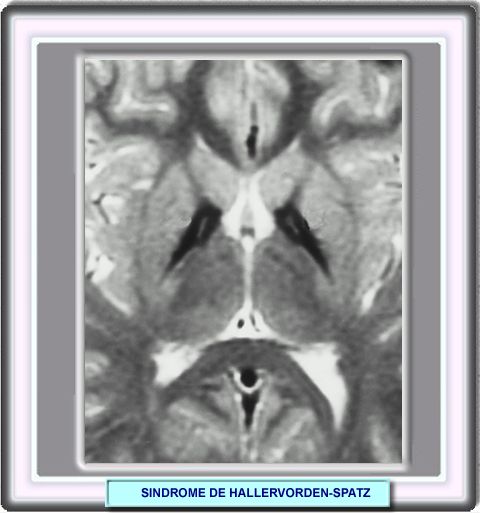

La Resonancia Nuclear Magnética (RNM) que en las etapas precoces es normal, posteriormente puede revelar una alteración característica. Consiste en una reducción marcada en la intensidad en T2 en ambos globus pallidus concordante con el depósito de hierro, con un área de señal incrementada en su parte central o ánteromedial debida a la necrosis. Este aspecto de sendos núcleos hipointensos en la profundidad de los hemisferios cerebrales conservando la zona central hiperintensa, ha sido llamado "signo del ojo de tigre".